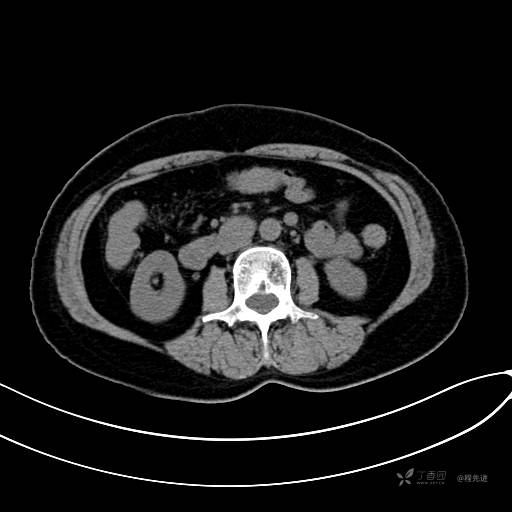

CT增强静脉期